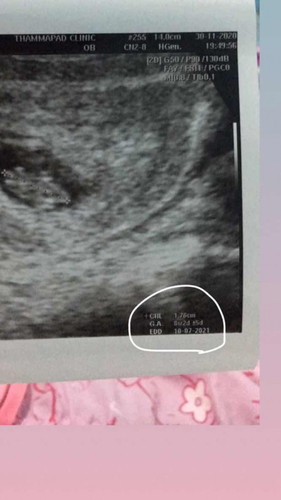

ตัวยาวหัวถึงก้นน่าจะ 1.76 cm อายุครรภ์ 6 สัปดาห์ 2 วัน +- 5วัน กำหนดคลอด วันที่ 10 เดือน 7 ปี 2021น่าจะประมาณนี้ค่ะ

ตัวแรก จากบนลงล่าง คือ ความยาว กลาง อายุน้องในท้อง ตัวล่างสุดท้าย วันกำหนดคลอดคะ